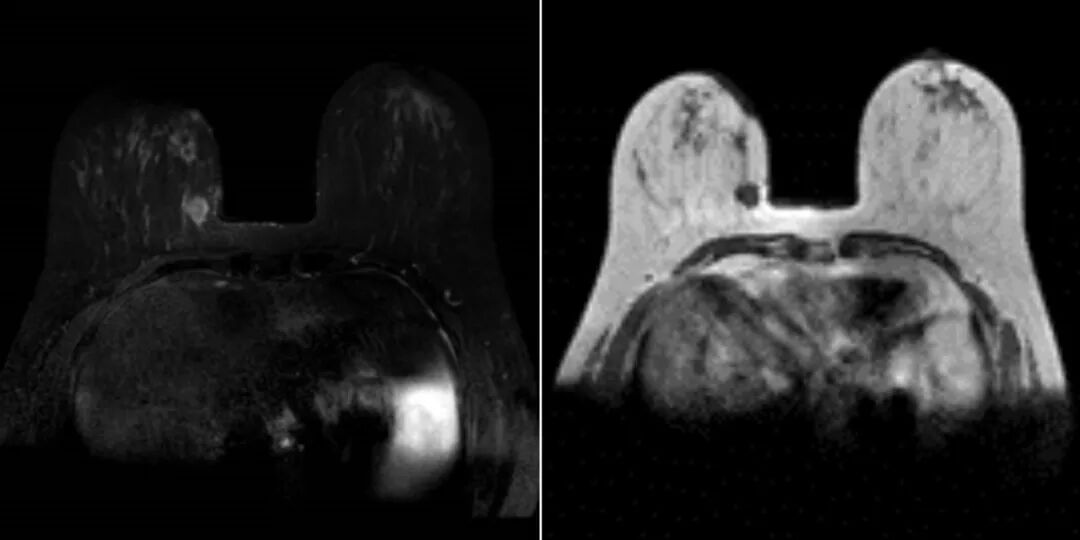

检查技术|乳腺癌各种影像学检查手段分析